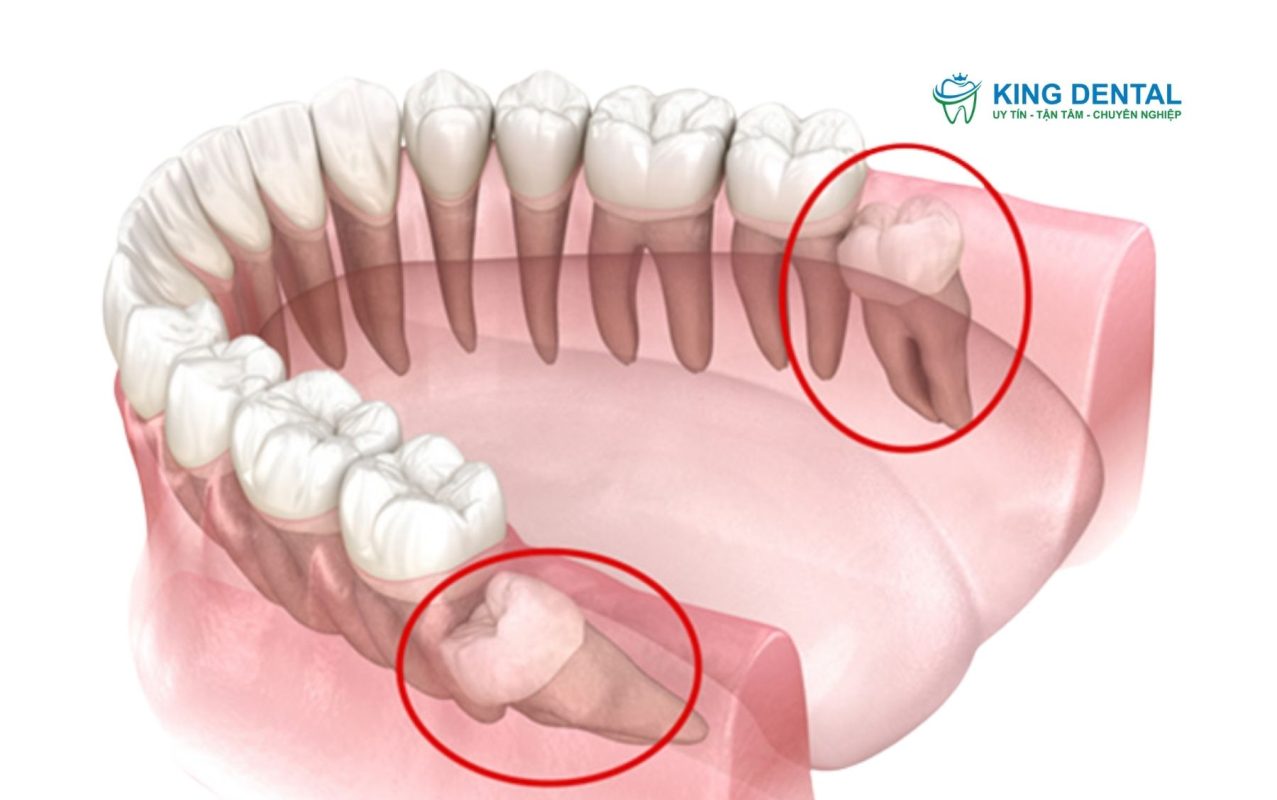

Răng khôn mọc lệch là tình trạng răng số 8 không mọc theo hướng thẳng đứng mà nghiêng sang răng số 7, đâm vào nướu hoặc bị kẹt trong xương hàm. Đây là một trong những vấn đề răng miệng phổ biến nhất ở người trưởng thành.

Răng khôn mọc lệch

• Sâu hoặc hủy hoại răng kế cận (răng số 7), do răng khôn “đè” lên răng bên cạnh.